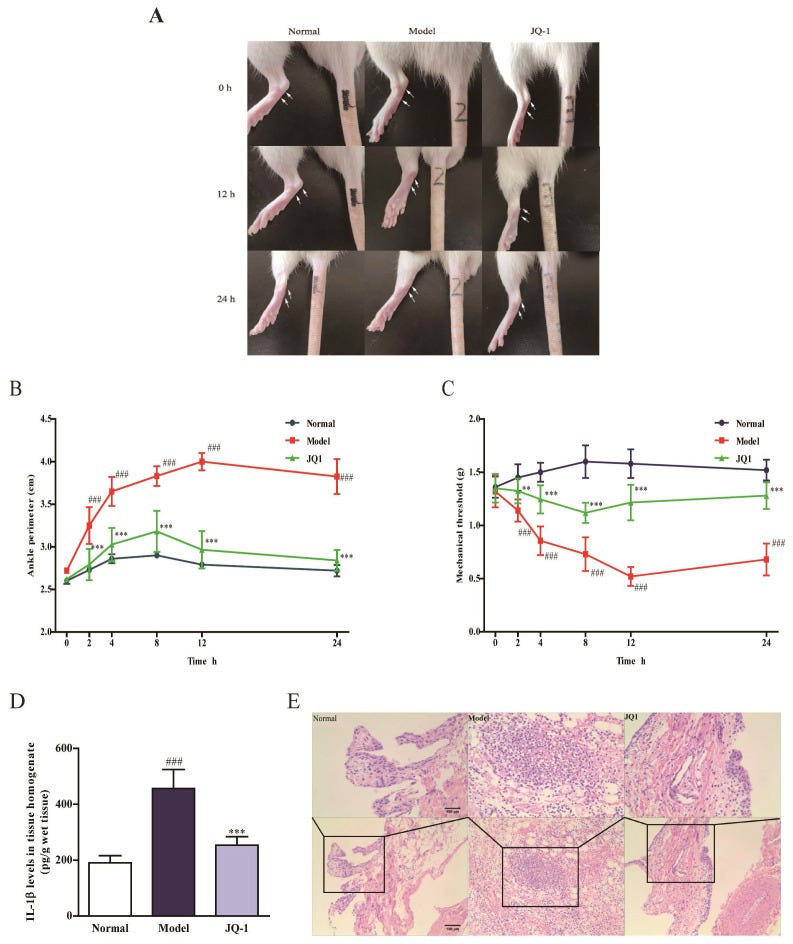

- Acute gouty arthritis

Finally in this review, from 2020 and Hao et al evaluated the effects of the BRD4 inhibitor JQ-1 on acute gouty arthritis. They found that JQ-1 could effectively attenuate symptoms induced in rats23:

Results: Pretreatment of JQ1 and BRD4 siRNA significantly suppressed pyroptosis and inhibited activation of p65 NF-κB signaling as well as NLRP3 inflammasome in THP-1 cells exposed to MSU. In vivo, JQ-1 administration could effectively attenuate joint swelling and synovial inflammation in rats treated by intra-articular injection of MSU. More importantly, MSU led to macrophage pyroptosis and Brd4/NF-κB/NLRP3/GSDMD signaling induction in rat synoviums, which was improved by JQ-1.

Conclusions: Our study identifies the role of BRD4 in MSU-induced pyroptosis through regulating NF-κB/NLRP3/GSDMD signaling pathways, which provides a potential target for treatment of acute gouty arthritis.